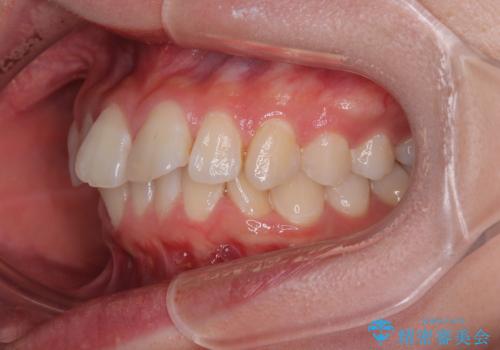

深い咬み合わせによる隙間 インビザライン矯正でコンプレックスを改善

- 上の前歯の隙間を気にして来院された患者様です。

インビザラインにより、上下の歯列を側方に拡大しつつ、前歯の隙間を閉じていくこととしました。

隙間の原因は強い咬合力や舌の突出癖、小帯の異常付着などがありますが、舌のトレーニングをしっかりと行いながら、装着時間を遵守して装着していただいたおかげで、スムーズに治療を終えることができました。